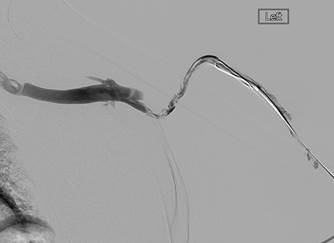

Fistulogram demonstrating thrombotic occlusion of a left brachiocephalic AV fistula (Note: arterial reflux of contrast).

Post 1st pass with AngioJet DVX Catheter (no thrombolytics used).